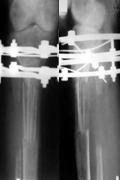

В ряде случаев при болезни Оллье (2 наблюдения) и костных кистах (1 наблюдение), когда требовалось не только заместить пострезекционный дефект кости, но и произвести компенсацию укорочения пораженной конечности, мы совмещали костную аллопластику с удлинением сегмента. Показанием к данному методу явилось укорочение конечности на более чем 4 см (рис. 5, а , б).

Рис. 5. Б-ой Ф., 15 лет: а – укорочение правой плечевой кости на почве солитарной кисты; б – рентгенограмма после проведения краевой резекции верхней трети правой плечевой кости, аллопластики Перфоостом и удлинения на имплантате в аппарате Илизарова

Аллопластика дистракционного регенерата перфоостом была выполнена у 6 больных (витамин-Д-резистентный рахит – у 3 пациентов, при ахондроплазии, гипохондроплазии и врожденном укорочении нижней конечности по одному случаю). Показанием для применения перфооста в указанных случаях являлась необходимость ускорения процессов регенерации. С этой целью аллоимплантаты изготавливались с высокой степенью деминерализации и условно назывались костным матриксом (рис. 6, а, б).

Рис. 6.Б-ой Ч., 14 лет. а – рентгенограммы незрелого регенерата до костной пластики; б – рентгенограммы после аллопластики дистракционного регенерата